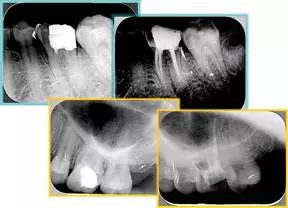

6. 钙化

常见有修复性钙化和增龄性钙化。下面为根管钙化 X 线片。

牙胶尖什么颜色​牙齿“晓”“技”|最全根管治疗的标准步骤,以及细节把握_https://www.jmylbn.com_新闻资讯_第26张

解决方法:( 1 )清楚根管系统解剖形态。( 2 )安全头的金刚砂钻开髓,低速球钻磨除钙化牙本( ET20 ,ET40 ,DG-16 )。( 3 )彻底去除髓腔周壁的牙本质龄。( 4 )借助化学性药剂,如EDTA 等。

( 5 )初锉选用 8# 或 10#K 锉,平衡力法探察到工作长度 , H锉上下提拉法使根管扩大,提高工作效率

7. 器械折断

右图及下图为器械折断的 X 线片。箭头处示折断器械。

牙胶尖什么颜色​牙齿“晓”“技”|最全根管治疗的标准步骤,以及细节把握_https://www.jmylbn.com_新闻资讯_第27张 牙胶尖什么颜色​牙齿“晓”“技”|最全根管治疗的标准步骤,以及细节把握_https://www.jmylbn.com_新闻资讯_第28张